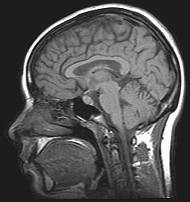

Compliance Consultants has "sat" as first and second chair on - and

assisted in the development of - many, many MRI & CAT (computer

axial tomography) scanners for FDA 510K applications.